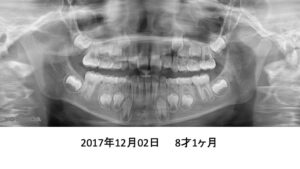

もう1症例、8才4ヶ月の患者さんです。

パノラマでは、永久歯が入るスペースが足りないように見えます。

4年後です。治療は何もしていません。

さらに2年後、全ての歯がちゃんと萌出しました。